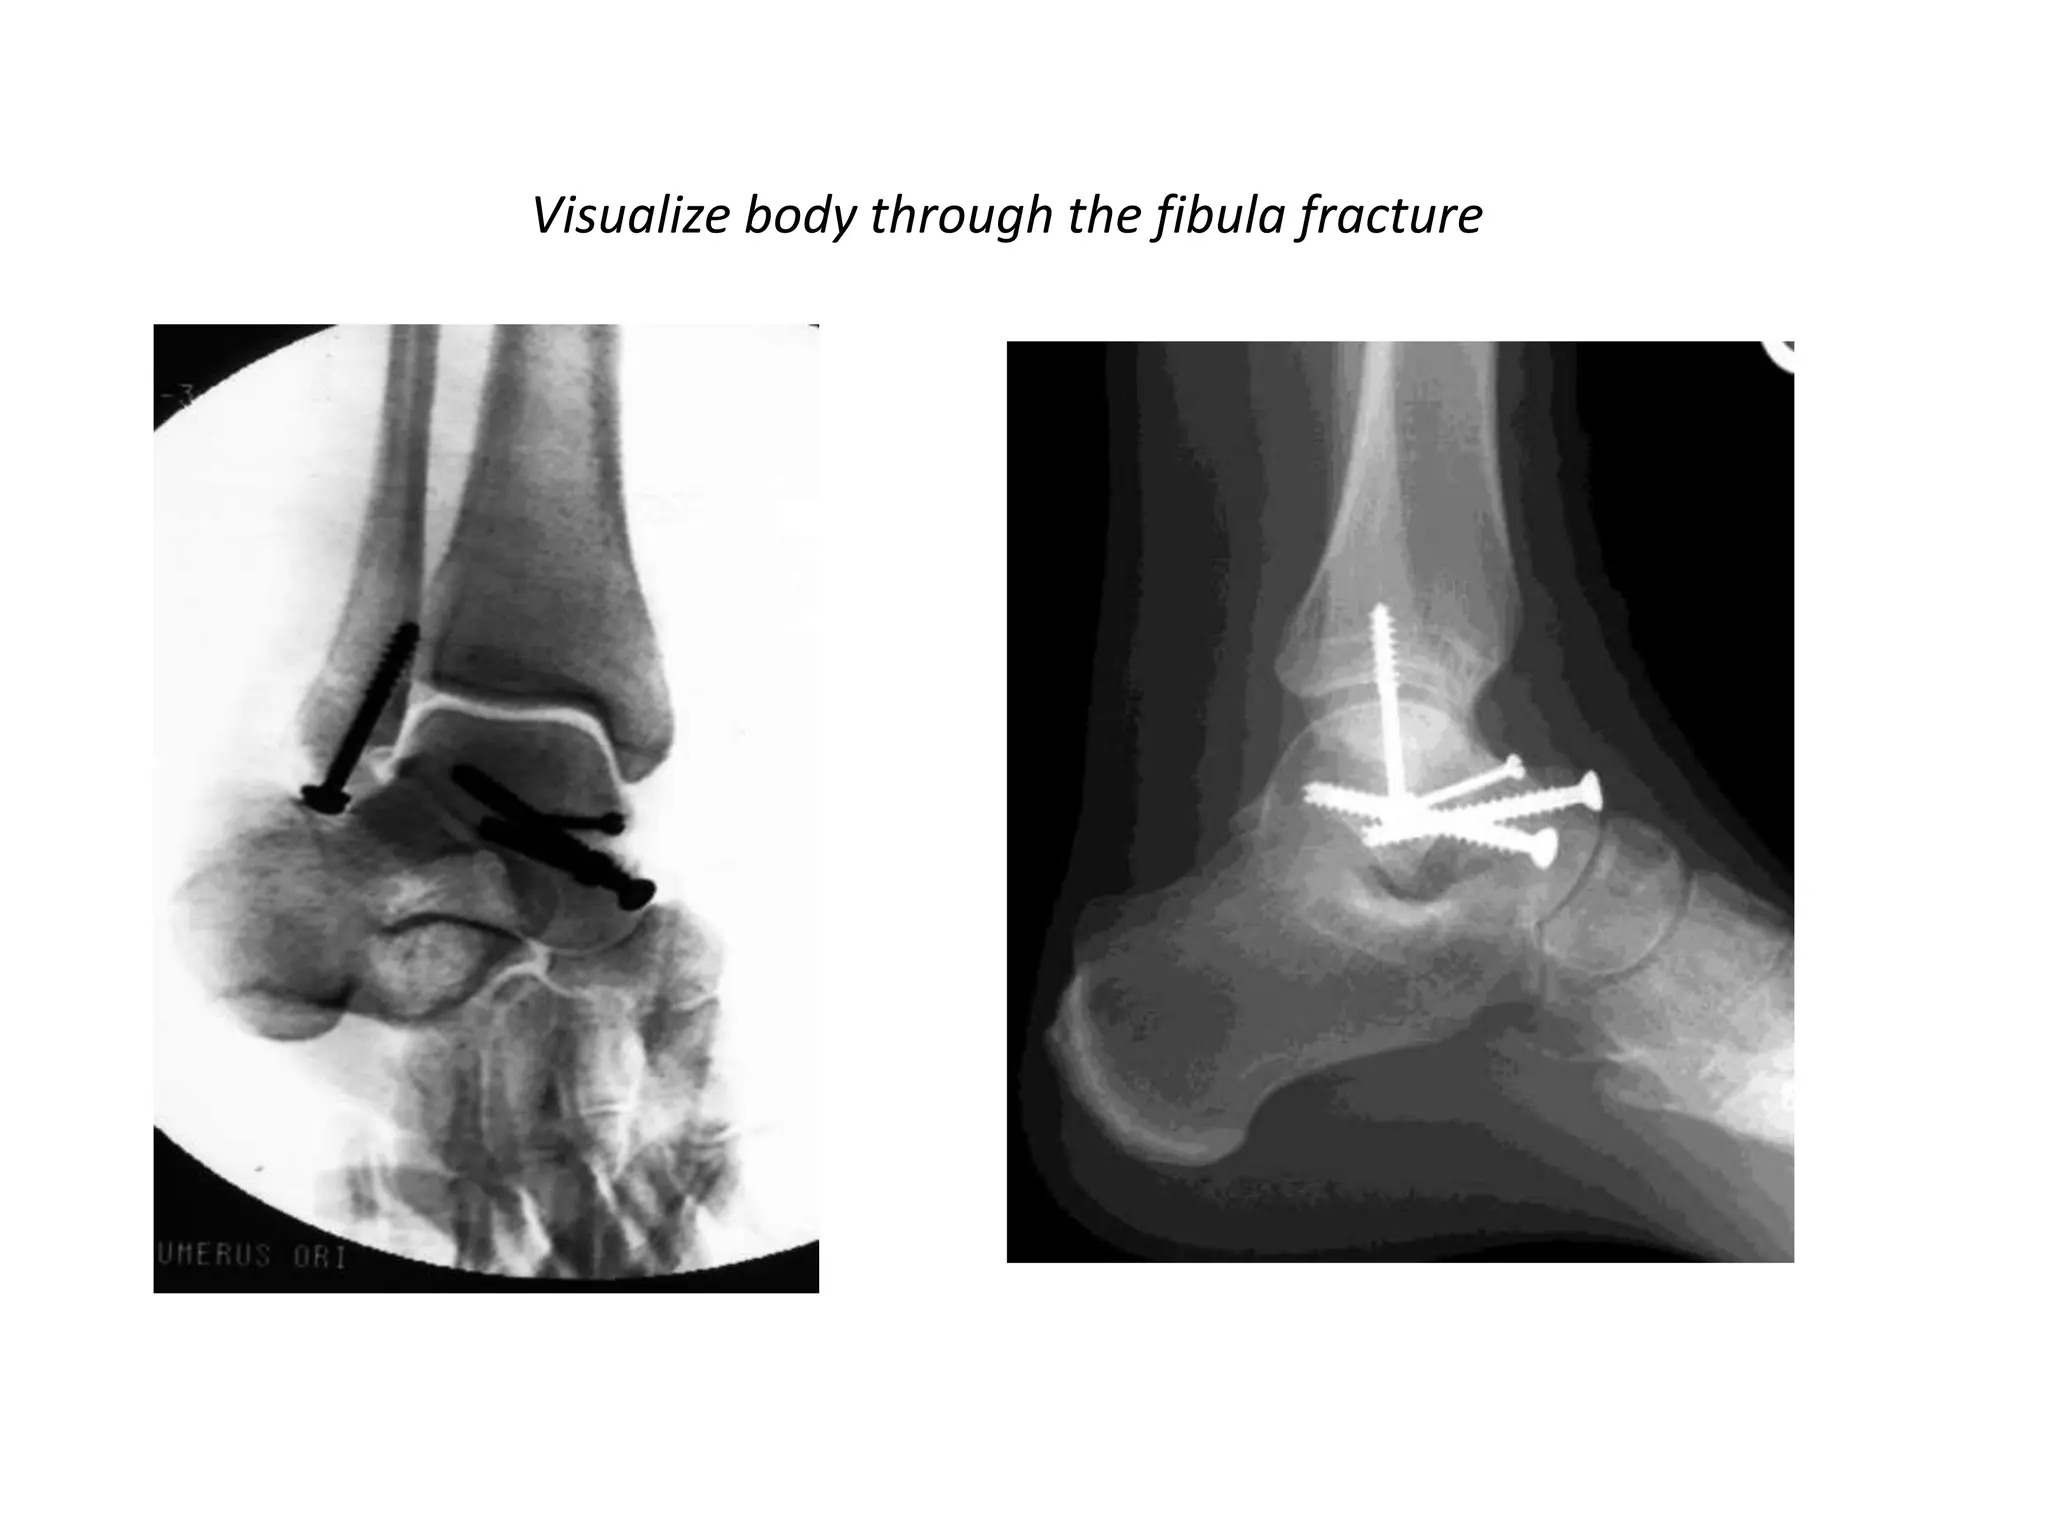

Visualize body through the fibula fracture

• Primary Arthrodesis:

– primary arthrodesis may be the appropriate

treatment for nonreconstructible fractures of the

talar body

– Primary arthrodesis offers the potential advantage

of earlier return to function compared to

unsuccessful attempts at open reduction and

internal fixation

Visualize body throughthe fibula fracture